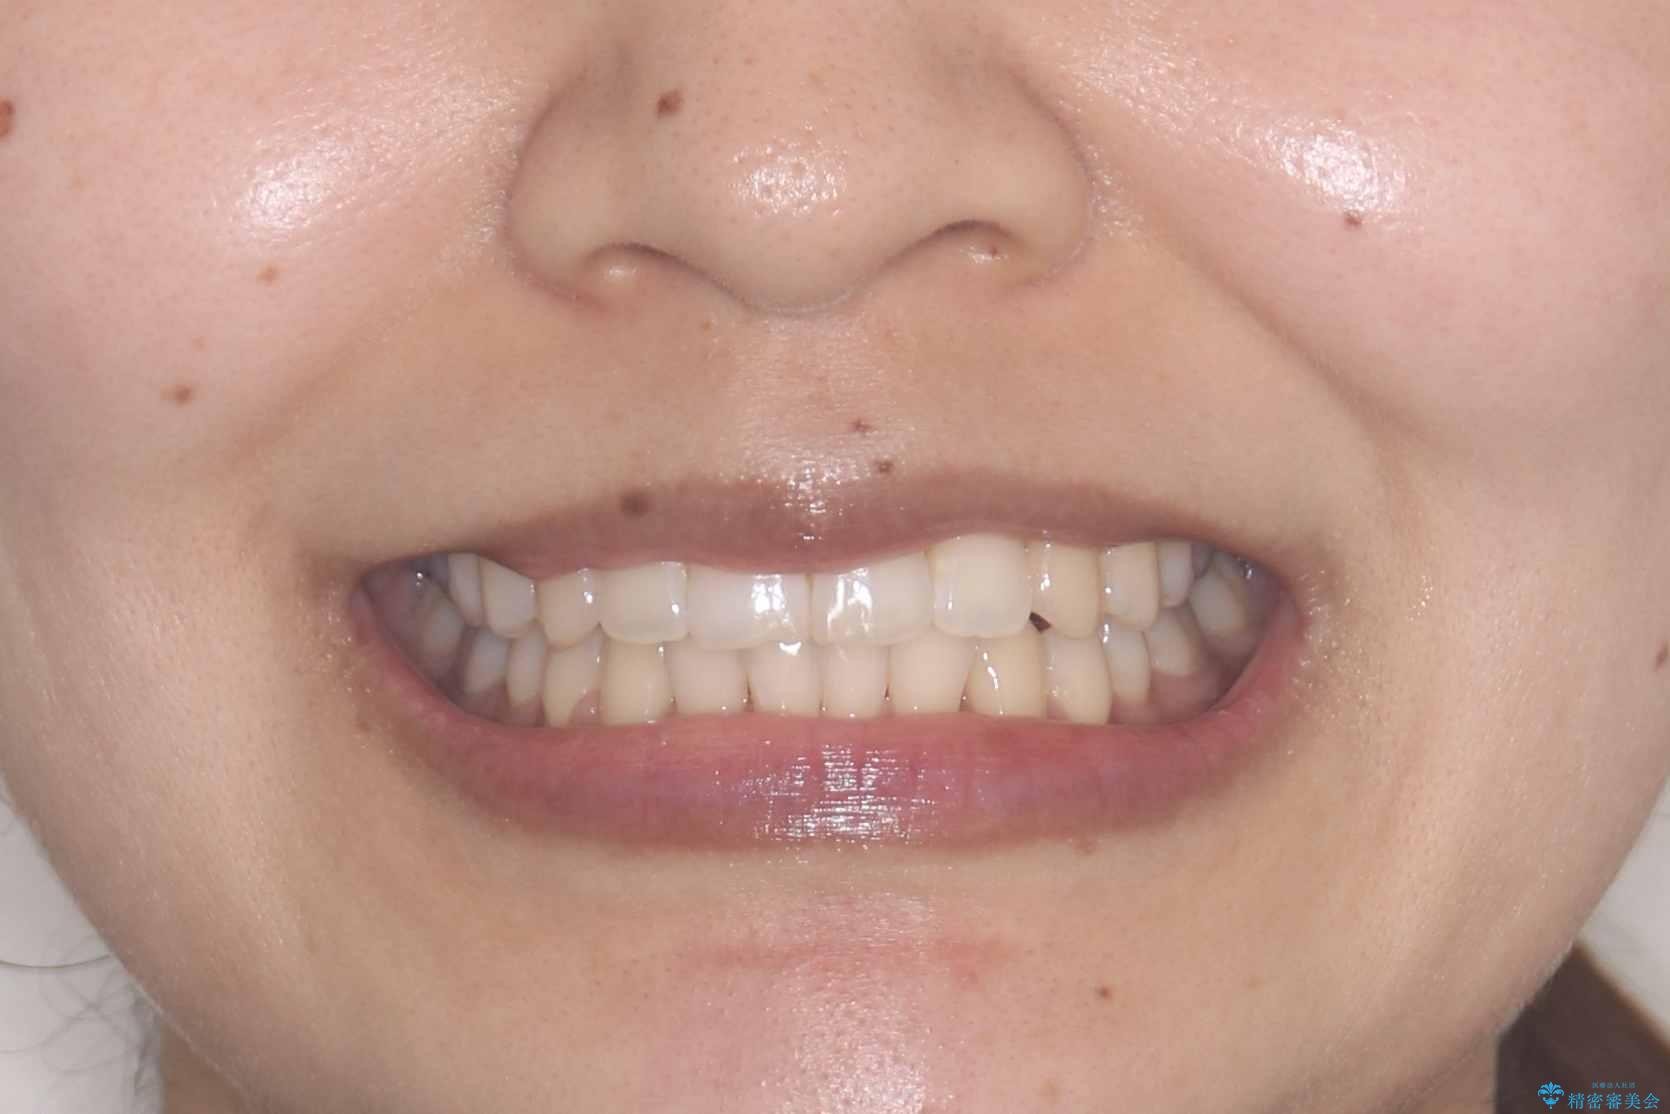

治療計画をしっかり立て、歯の移動量や力のコントロールを最適化することで、約1年という短期間で矯正治療を終了することができました。

「矯正は時間がかかる」というイメージをお持ちの方も多いですが、症例によっては、非抜歯でも短期間で改善が可能な場合があります。

治療後は歯並び・かみ合わせともに大きく改善し、患者様にも大変ご満足いただけました。